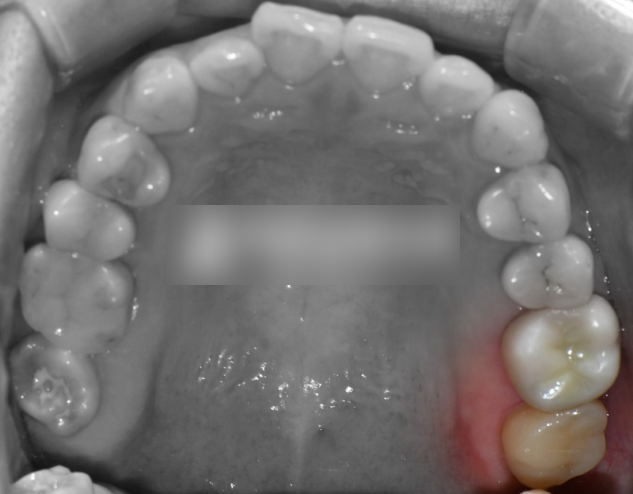

이후 크라운 보철을 씌우면

모든 과정이 마무리됩니다.

검게 썩어서 교합면 일부가

떨어져 나간 이전과 달리,

실제 자연치와 유사한 크라운이 올려져

있는 것으로 보여집니다.

수복이 완료되었다면,

음식을 잘 씹을 수 있도록 바이트 체크를 통해

먼저 닿거나 닿지 않는 곳이 있는지

마지막으로 점검합니다.